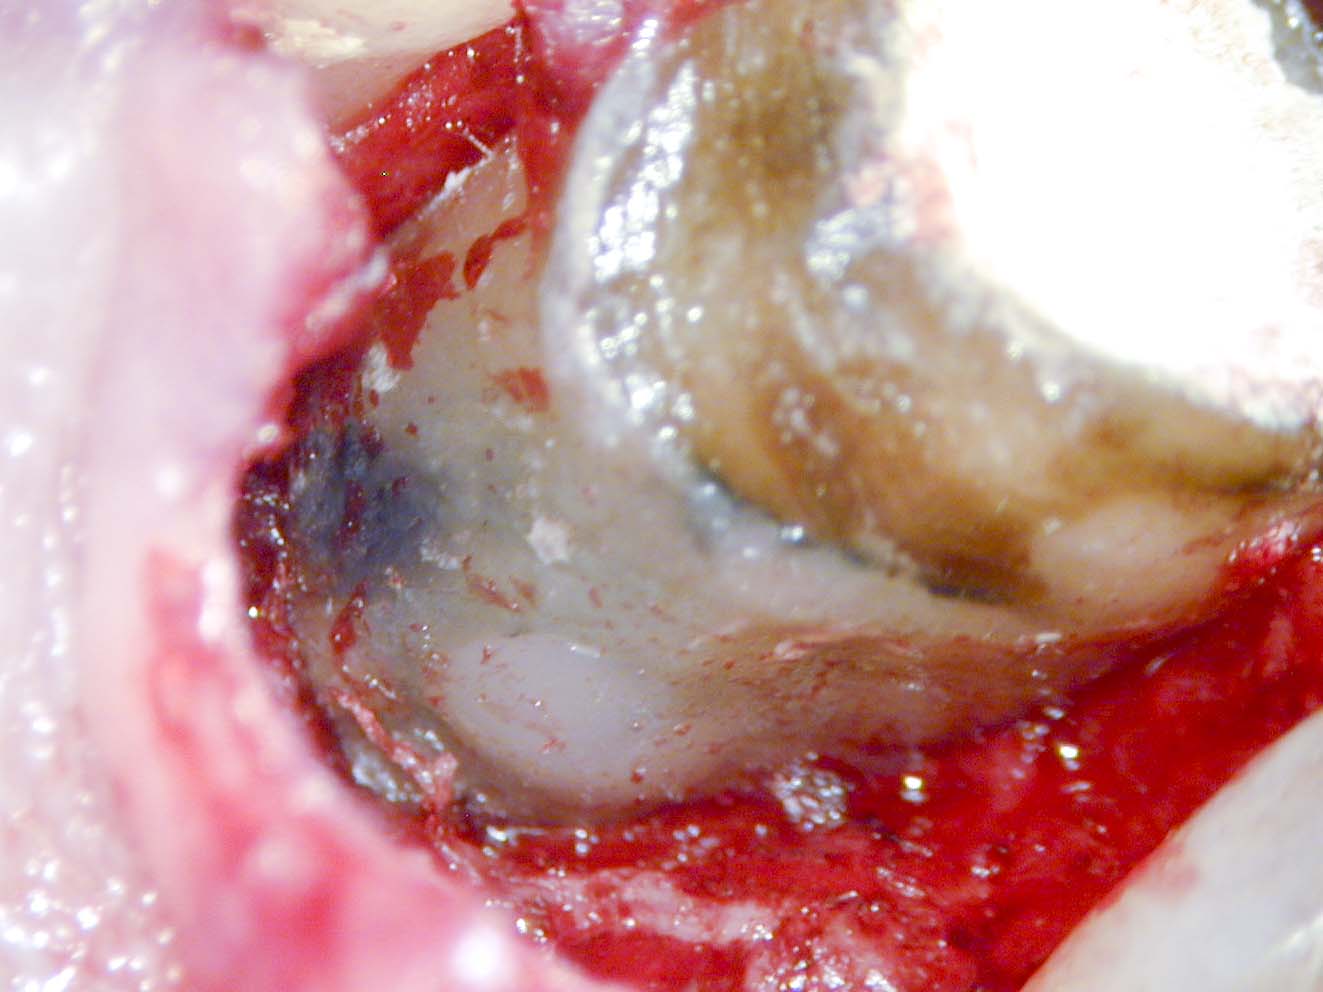

Apikale Resorption-6

Veröffentlicht 9. Juni 2009 am 1323 × 992 in Saving hopeless teeth (VI), Apikale Aufhellung (9) – Zahn 21 mit Fistel, WSR, SSA, tiefen Taschen und Resorption